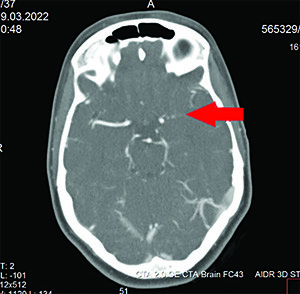

Пациентке выполнены КТ головного мозга и КТ-ангиография.

При выполнении КТ-ангиографии головного мозга выявлена окклюзия левой ВСА до М1-сегмента (см. рис. 1).